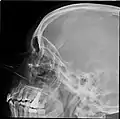

X-ray images and illustrations

Paranasal sinuses radiograph (lateral)